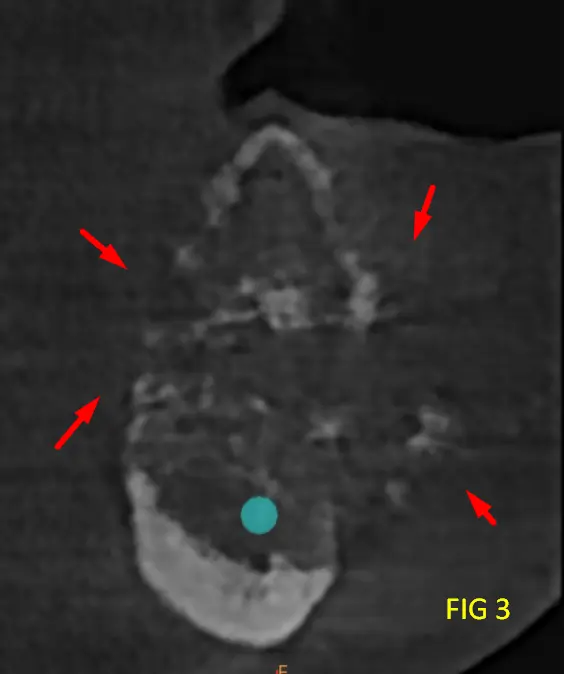

Presenta tabiques óseos finos que delimitan compartimentos irregulares con expansión y adelgazamiento de las corticales óseas, con áreas de compromiso cortical. La relación cercana con el conducto dentario inferior, sin evidencia clara de invasión, pero con desplazamiento y borramiento en sectores de dicha pared del conducto.

En cortes transversales se aprecia la naturaleza infiltrativa de la lesión, con forma de rayos de luz, sin límites netos, característica típica del mixoma Odontogénico.